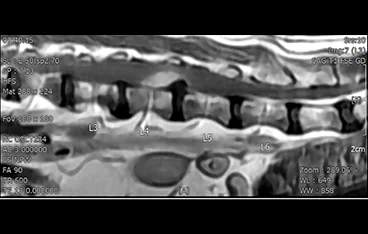

• 경추 디스크 MRI

• 경추 디스크

• 흉요추 디스크 MRI

• 흉요추 디스크